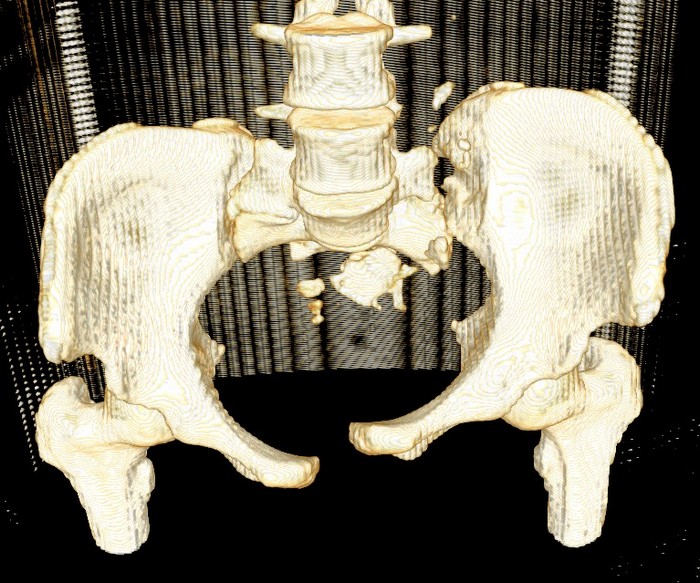

Девочка 14 лет. Кататравма (падение с высоты 4-5 этажа). Вертикально нестабильный перелом таза со смещением, разрывом лонного и левого подвздошно-крестцового сочленения, перелом крестца, открытый перелом костей голени. Ребёнок оперирован на 10-е сутки после травмы - выполнили максимально возможную репозицию на ортопедическом столе, синтез лонного сочленения реконструктивной пластиной (из имеющихся пластин - на 7 дыр - самая длинная, получилось только по 2 шурупа с каждой стороны, поэтому пришлось подстраховаться проволокой), АВФ. Задний комплекс не фиксировали ввиду отсутствия канюлированных (да и неканюлированных)шурупов должной длинны.В настоящий момент перед нами стоит вопросов:1. Обязательно ли фиксировать подвздошно-крестцовое сочленение, либо фиксации АВФ будет достаточно? Аппарат стоит достаточно стабильно, девочка при перемещениях в пределах постельного режима болевых ощущений не испытывает.2. Что делать с отломком крестца, который довольно значительно смещён кпереди? В настоящий момент никаких проблем с дефекацией у больной нет, хотя, глядя на КТ, создаётся впечатление, что отломок прямо-таки лежит на прямой кишке. Репонировать-фиксировать? Просто удалить? Вообще не трогать? Не создаст ли он в дальнейшем проблем во время родов?Хотелось бы знать мнение уважаемых коллег.Заранее спасибо.